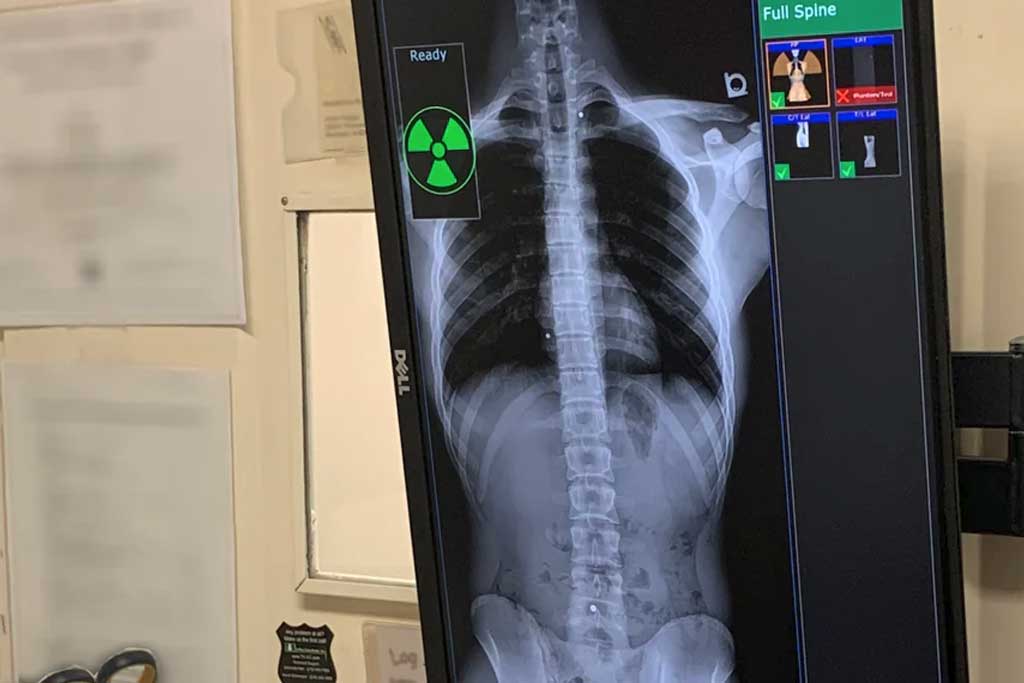

رادیولوژی فول اسپاین (Full Spine Radiography) روشی تخصصی در تصویربرداری پزشکی است که به وسیله اشعه ایکس، تمام ستون فقرات از مهرههای گردنی (سرویکال) تا مهرههای خاجی و دنبالچه را در یک تصویر بلند یا به صورت تصاویر متوالی بههمچسبیده نمایش میدهد.

این روش نسبت به رادیوگرافیهای محدود (مانند رادیوگرافی فقط کمر یا گردن) مزیت بزرگی دارد: پزشک میتواند کل ساختار ستون فقرات را در یک نگاه ارزیابی کند و ارتباط بین بخشهای مختلف را بسنجد. بهویژه در بررسی اختلالات انحنای ستون فقرات، این ویژگی حیاتی است.

ستون فقرات ساختاری پیچیده است و هرگونه تغییر در یک بخش میتواند سایر بخشها را تحت تأثیر قرار دهد. به عنوان مثال، کیفوز شدید در ناحیه قفسه سینه ممکن است منجر به تغییرات جبرانی در ناحیه کمری شود. تصویربرداریهای محدود قادر به نشان دادن این ارتباطها نیستند. رادیولوژی فول اسپاین امکان میدهد:

- بررسی همزمان مهرههای گردنی، سینهای و کمری

- تشخیص انحرافهای ترکیبی (مانند اسکولیوز همراه با کیفوز)

- اندازهگیری دقیق زاویههای انحنا با روش Cobb

- پیگیری روند درمان یا جراحی اصلاحی